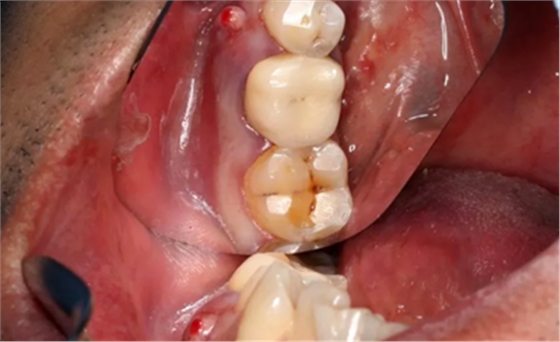

2、术前口腔内照片

46牙烤瓷冠修复,牙周红肿,叩痛,松2度。骨吸收波及邻牙,邻牙牙周情况不佳,45牙松2度,47牙松1度。

(摄于2016年8月31日,反光板协助拍摄)